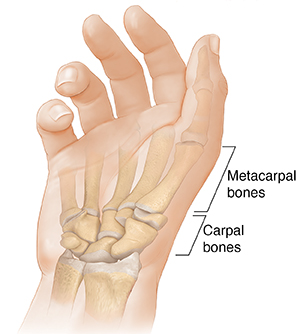

The base of the thumb where it meets the hand is called the carpometacarpal (CMC) joint. This joint lets the thumb move freely in many directions. It provides strength so the hand can grasp and grip.

A smooth tissue called cartilage lines and cushions the bones of the CMC joint. Using the thumb puts stress on the joint. Over time, this can lead to the breakdown of the cartilage in the joint. This is known as osteoarthritis. With this condition, bones of the joint may rub together. They may become irritated and rough. This keeps the joint from moving smoothly and can lead to pain.